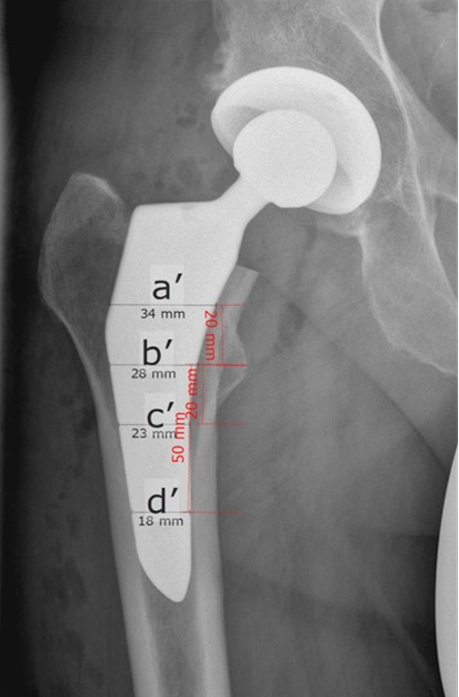

Hip stem migration (subsidence) was evaluated on anteriorposterior radiographs of the pelvic in a standing position with a film-focus-distance of 115 cm performed 5 days, 3 months and two years postoperative. The validated software “FXA” of the independent imaging core lab (RAYLYTIC, Leipzig, Germany) was used [26-28]. The software matches two images (24 months and 3 months vs. 5 days postop) using a normalized 2D grayscale cross-correlation algorithm in an iterative process using the evolutionary optimization algorithm CMA-ES [29]. Moreover, the radiographs were analyzed for radiolucent lines around the stem. The radiographs were analyzed retrospectively. The following parameters were measured on the postoperative radiographs (Figure 2,3): The Canal Flare Index (CFI), the Canal Fill Ratio (CFR), the Stem Angulation (SA) and calculated as potential influencing factors for subsidence as well as the clinical parameters: gender, weight, BMI, age and stem size.

Figure 2a: Description of the different measurements for calculating the Canal Fill Index (CFI) and Canal Fill Ratio (CFR). Fig 2a: preoperative x-ray, Fig 2b: postoperative x-ray. Canal Flare Index (CFI = a/e), Canal-Calcar Ratio (CCR = e/b); Canal Fill Ratios (CFR P1) at 2 cm above the lesser trochanter (P1 = a’/a), CFR P2 at the lesser trochanter (P2 = b’/b), CFR P3 at 2 cm below the lesser trochanter (P3 = c’/c), CFR D1 at 5 cm below the lesser trochanter (D1 = d’/d).

Figure 2b: Description of the different measurements for calculating the Canal Fill Index (CFI) and Canal Fill Ratio (CFR). Fig 2a: preoperative x-ray, Fig 2b: postoperative x-ray. Canal Flare Index (CFI = a/e), Canal-Calcar Ratio (CCR = e/b); Canal Fill Ratios (CFR P1) at 2 cm above the lesser trochanter (P1 = a’/a), CFR P2 at the lesser trochanter (P2 = b’/b), CFR P3 at 2 cm below the lesser trochanter (P3 = c’/c), CFR D1 at 5 cm below the lesser trochanter (D1 = d’/d).